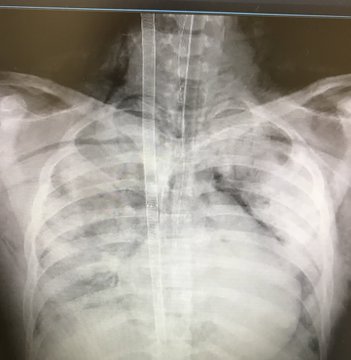

تداول عدد من المغردين، عدة صور قال عنها ناشرها الطبيب إباء عبدالله جستنيه، إنها صور لـ4 أشعات للصدر في 4 أيام لطفل عمره 17 سنة.

ووجه جستنيه تحذيرًا، لمن يدخن السجائر الإلكترونية، وقال: “أتانا للطوارئ بضيق النفس. دخلناه التنويم، ثم العناية، والآن هو على جهاز الإنعاش ECMO لالتهاب رئوي حاد بسبب تدخينه السيجارة الإلكترونية… انظر بعينك، المرض فتاك والقرار قرارك”.

وحظيت الصور بتفاعل كبير، بعد أن عبر المواطنون عن إحساسهم بالخطر من السجائر على المراهقين والشباب في مختلف الأعمار، بينما شكك آخرون بأضرار السجائر الإلكترونية، حيث قال معاذ الخطيب: “قد يكون التهابًا فيروسيًا، إلى الآن لا يوجد أي دليل في أي مكان في العالم أن السجائر الإلكترونية تسبب متلازمة التهاب الصدر ARDS. والأشياء المنشورة عالميًا مازالت تعترف بأن العلاقة غير مؤكدة بين التهاب الرئة والسيجارة الإلكترونية، ملاحظة: السيجارة العادية تقتل ١٧٠٠ شخص يوميًا”.